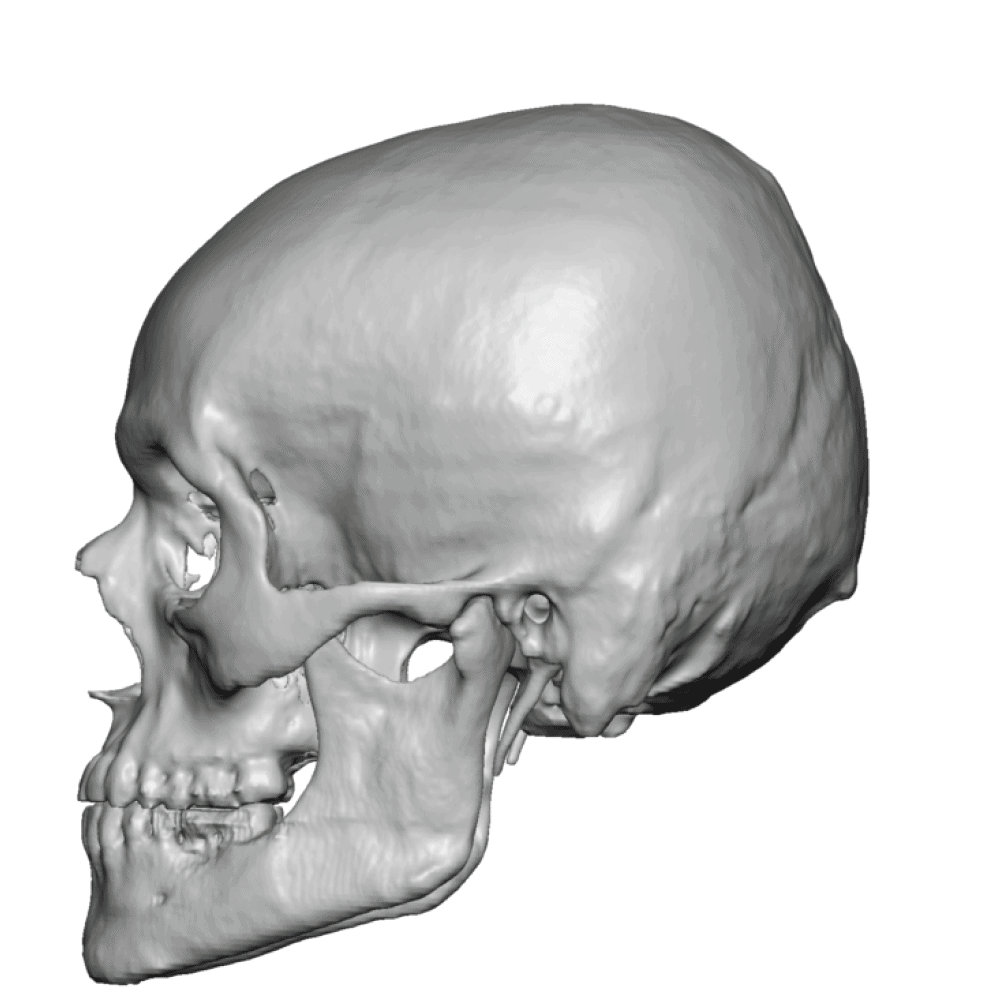

Severe narrowing skull deformity from prior sagittal craniosynostosis repair as an adult.

Complete replacement of entire skull by a custom implant with temporal fat injections.